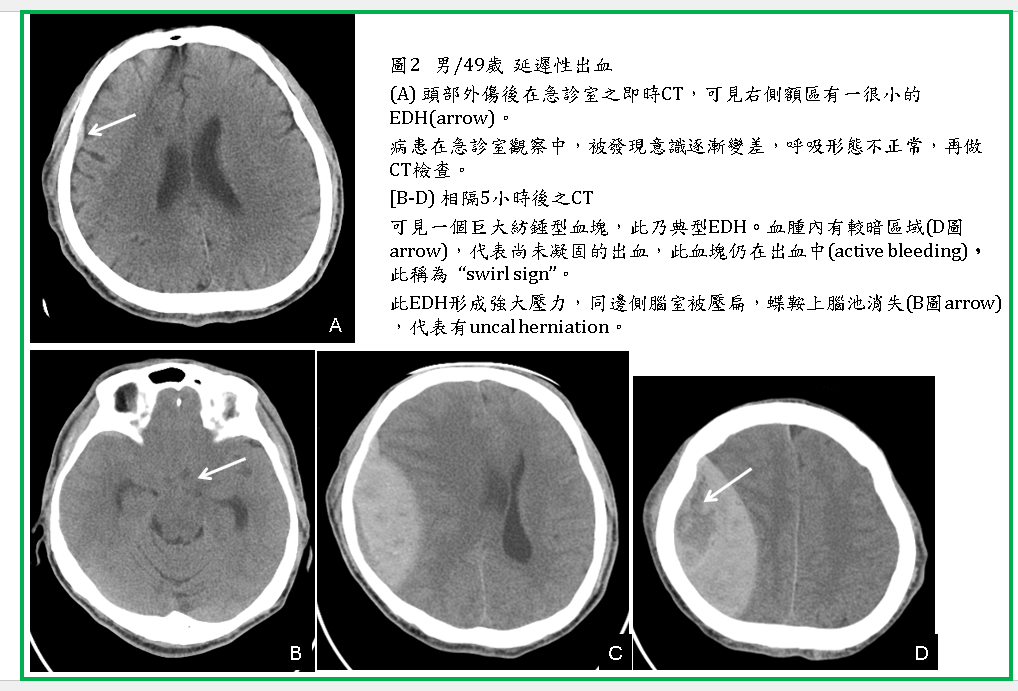

如果在做CT時,血腫內仍有動脈在出血,則血腫內含有未凝固的血液時,可在血腫內看到較灰或較暗的區域,使整個血腫看起來像漩渦狀(swirl sign) (圖2,3) 。

EDH通常會造成很強的腫塊效應(mass effect),腫塊效應太強時,會造成海馬鉤及小腦天幕下疝脫(uncal and transtentorial herniations) (圖2),因此經常需要緊急手術去除EDH。